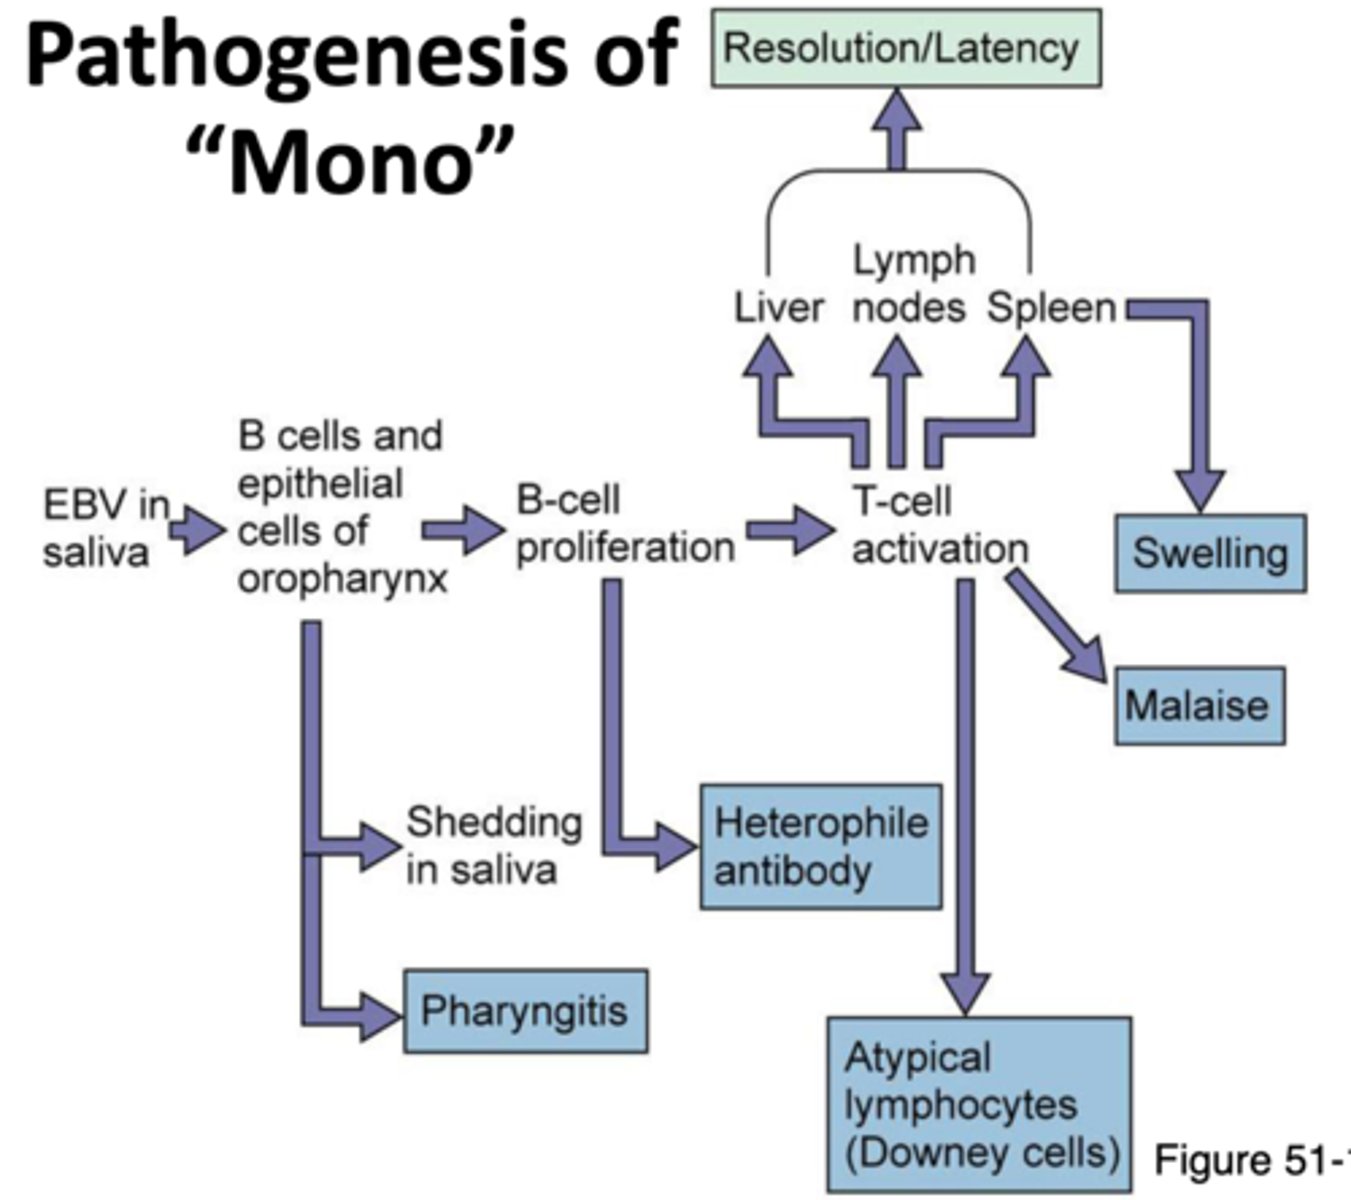

Pathogenesis of mono

EBV enters and multiplies in epithelial cells in mouth --> Spreads to B cells in the throat --> Infected B cells multiply --> Signs and symptoms --> Cytotoxic T cells and NK cells destroy infected B cells --> Recovery